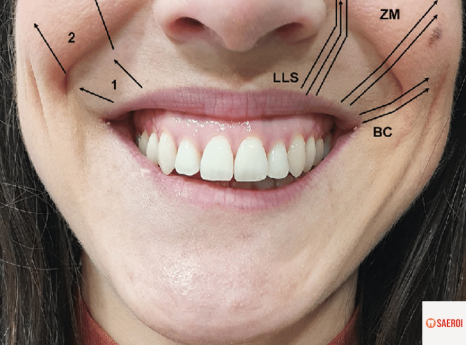

(2) 입술 주변 근육의 과도한 활성

입술 주변에는

우리가 웃을 때 미소를 짓게 만들어 주는

여러 근육들이 존재합니다.

이러한 근육들이 과도하게 활성화되는 경우,

즉, 웃을 때 입꼬리와 입술을 위로 올리는 근육이

너무 과하게 위로 당기는 힘을 주게 되면

커튼이 위로 올라가듯이

그 아래의 잇몸이 과하게 보이게 됩니다.